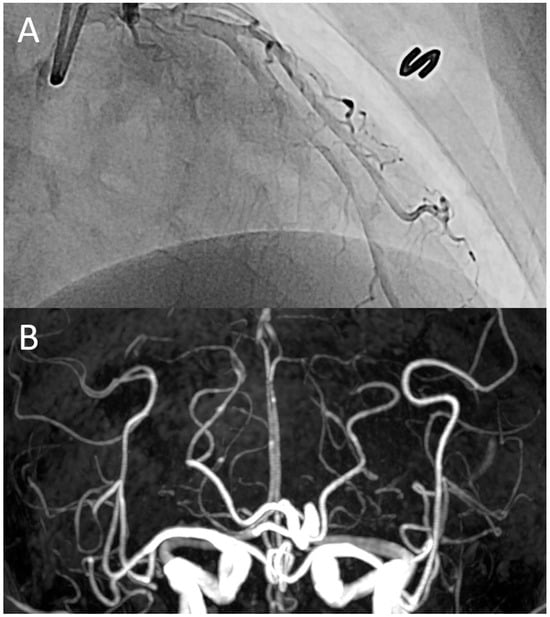

According to the diagnostic criteria outlined in this study, we identified eight patients with extracerebral vasoconstriction. Their characteristics, diagnostic processes, treatments, and clinical outcomes are summarized in Table 2. In the case of a 52-year-old woman, coronary vasospasm was confirmed through invasive coronary angiography (Figure 1). One patient underwent coronary computed tomography angiography (CCTA), while the other two underwent abdominal computed tomography angiography. None of these patients exhibited significant stenoses in their extracerebral arteries or other organic lesions. Four patients were diagnosed with possible extracerebral vasoconstriction, as they did not undergo a diagnostic work-up for extracerebral pain. All patients demonstrated an excellent response to vasodilator treatment. No patients reported neurovascular or extracerebral complications during the bout of RCVS.

Figure 1. A representative case: a 52-year-old woman was admitted to the cardiology division due to recurrent episodes of sudden, severe chest pain, accompanied by thunderclap headaches and abdominal cramping. Invasive coronary angiography revealed diffuse coronary vasospasm (A), while time-of-flight magnetic resonance angiography demonstrated diffuse vasoconstriction in the distal segments of the intracranial arteries (B). These findings suggest a co-occurrence of vasoconstriction in both the heart and brain.